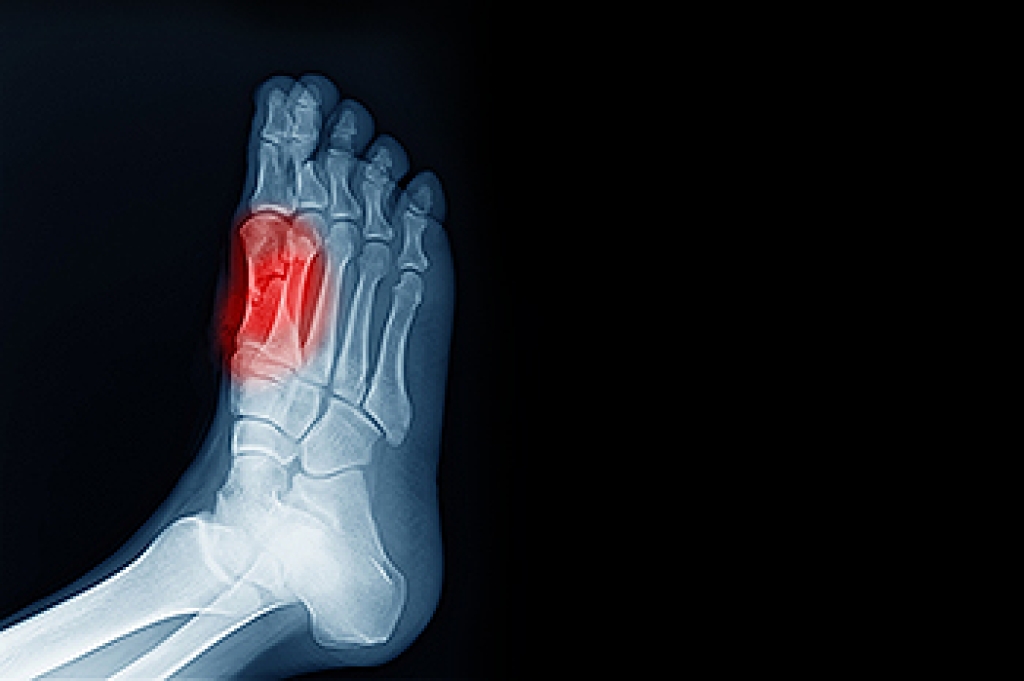

Puncture wounds to the feet are often caused by sharp objects, such as nails, glass, or thorns. Animal bites.might also cause puncture wounds. They should never be considered minor injuries. Even the smallest puncture wounds can trap bacteria deep beneath the skin. If care is delayed, this increases the risk of infection, abscess formation, joint involvement, or bone infection. Symptoms may initially appear mild, but pain, swelling, redness, or drainage can develop days or even weeks later. A podiatrist evaluates the depth, location, and cause of the injury, checks for retained foreign material, and assesses surrounding nerves, tendons, joints, and bone. Diagnostic imaging and laboratory testing may be used to detect hidden damage or early infection. Prompt medical management can significantly reduce the risk of serious complications for people with diabetes, who may lack sensation in the feet. For help with foot pain caused by a puncture, it is suggested that you make an appointment with a podiatrist for an exam, diagnosis, and treatment.